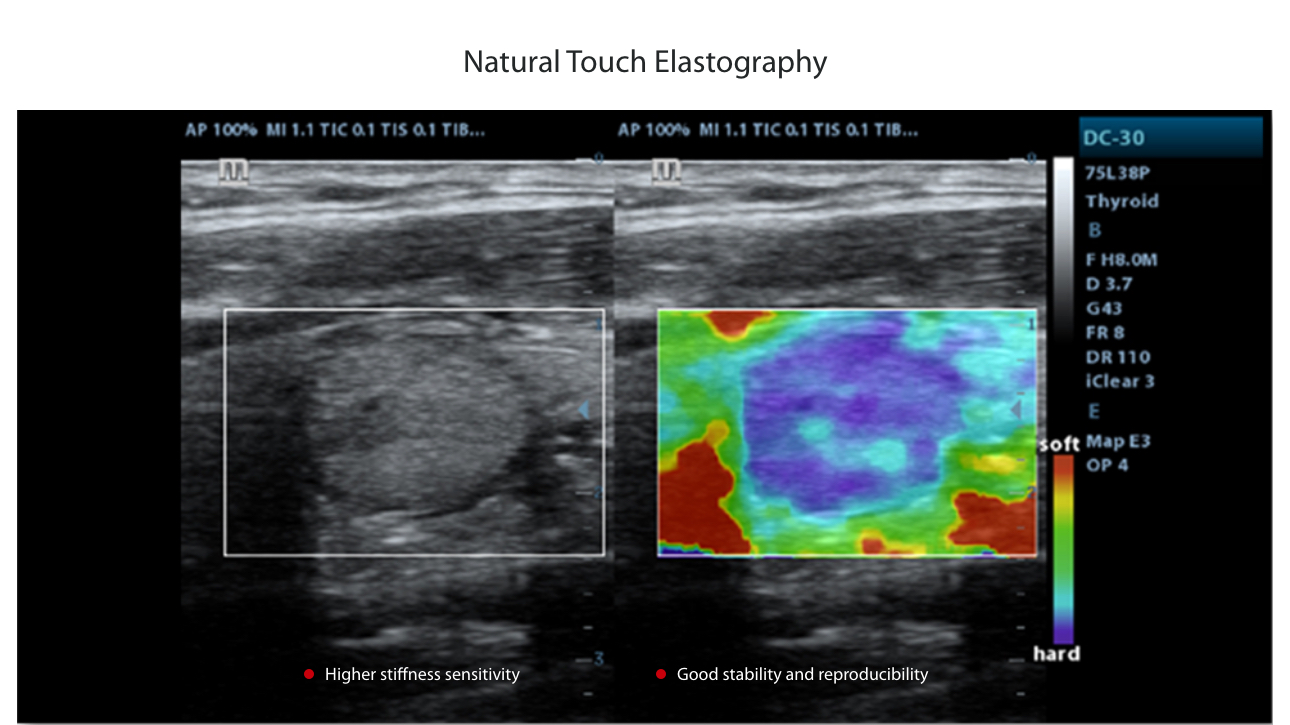

- Natural Touch Elastography, Based on Mindray’s latest patented technology, natural touch elastography reduces dependence on user operation technique, improving the operator’s reproducibility for higher clinical utility.

| Radiology Functions | Auto IMT Measurement, EFV (Extended Field of View), Elastography (RTE) |